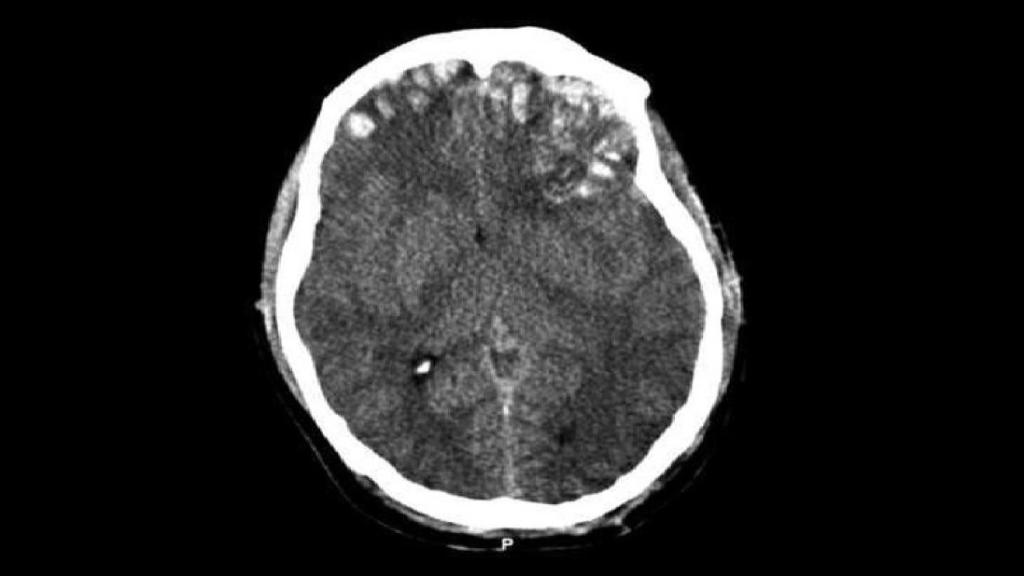

Un tac muestra la fractura craneal con hundimiento de un sujeto.

Un tac muestra la fractura craneal con hundimiento de un sujeto. Wikipedia